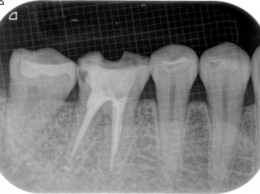

根管治療は、根の彎曲度合いや、根の形態(2つの根管が潰されて癒合していたり)等を前もって知る事で飛躍的に精度が上がります。現に他院のやり直しの根管治療では、根の見落としや根管を掃除する際に穿孔していたりという事を、頻繁に発見します。経験や手探りによる治療には限界があるという事ではないでしょうか?

清潔な無菌的な根管の清掃が終了したら、緊密に根管充塡を行います。レントゲンで白く写る部分です。

根管治療の最後の処置です。根管の解剖学的な形態、彎曲度合い等によって数種類の根管充塡システムを当院では使い分けています。

- 根の治療は終わったと言われたそうですが、、、、